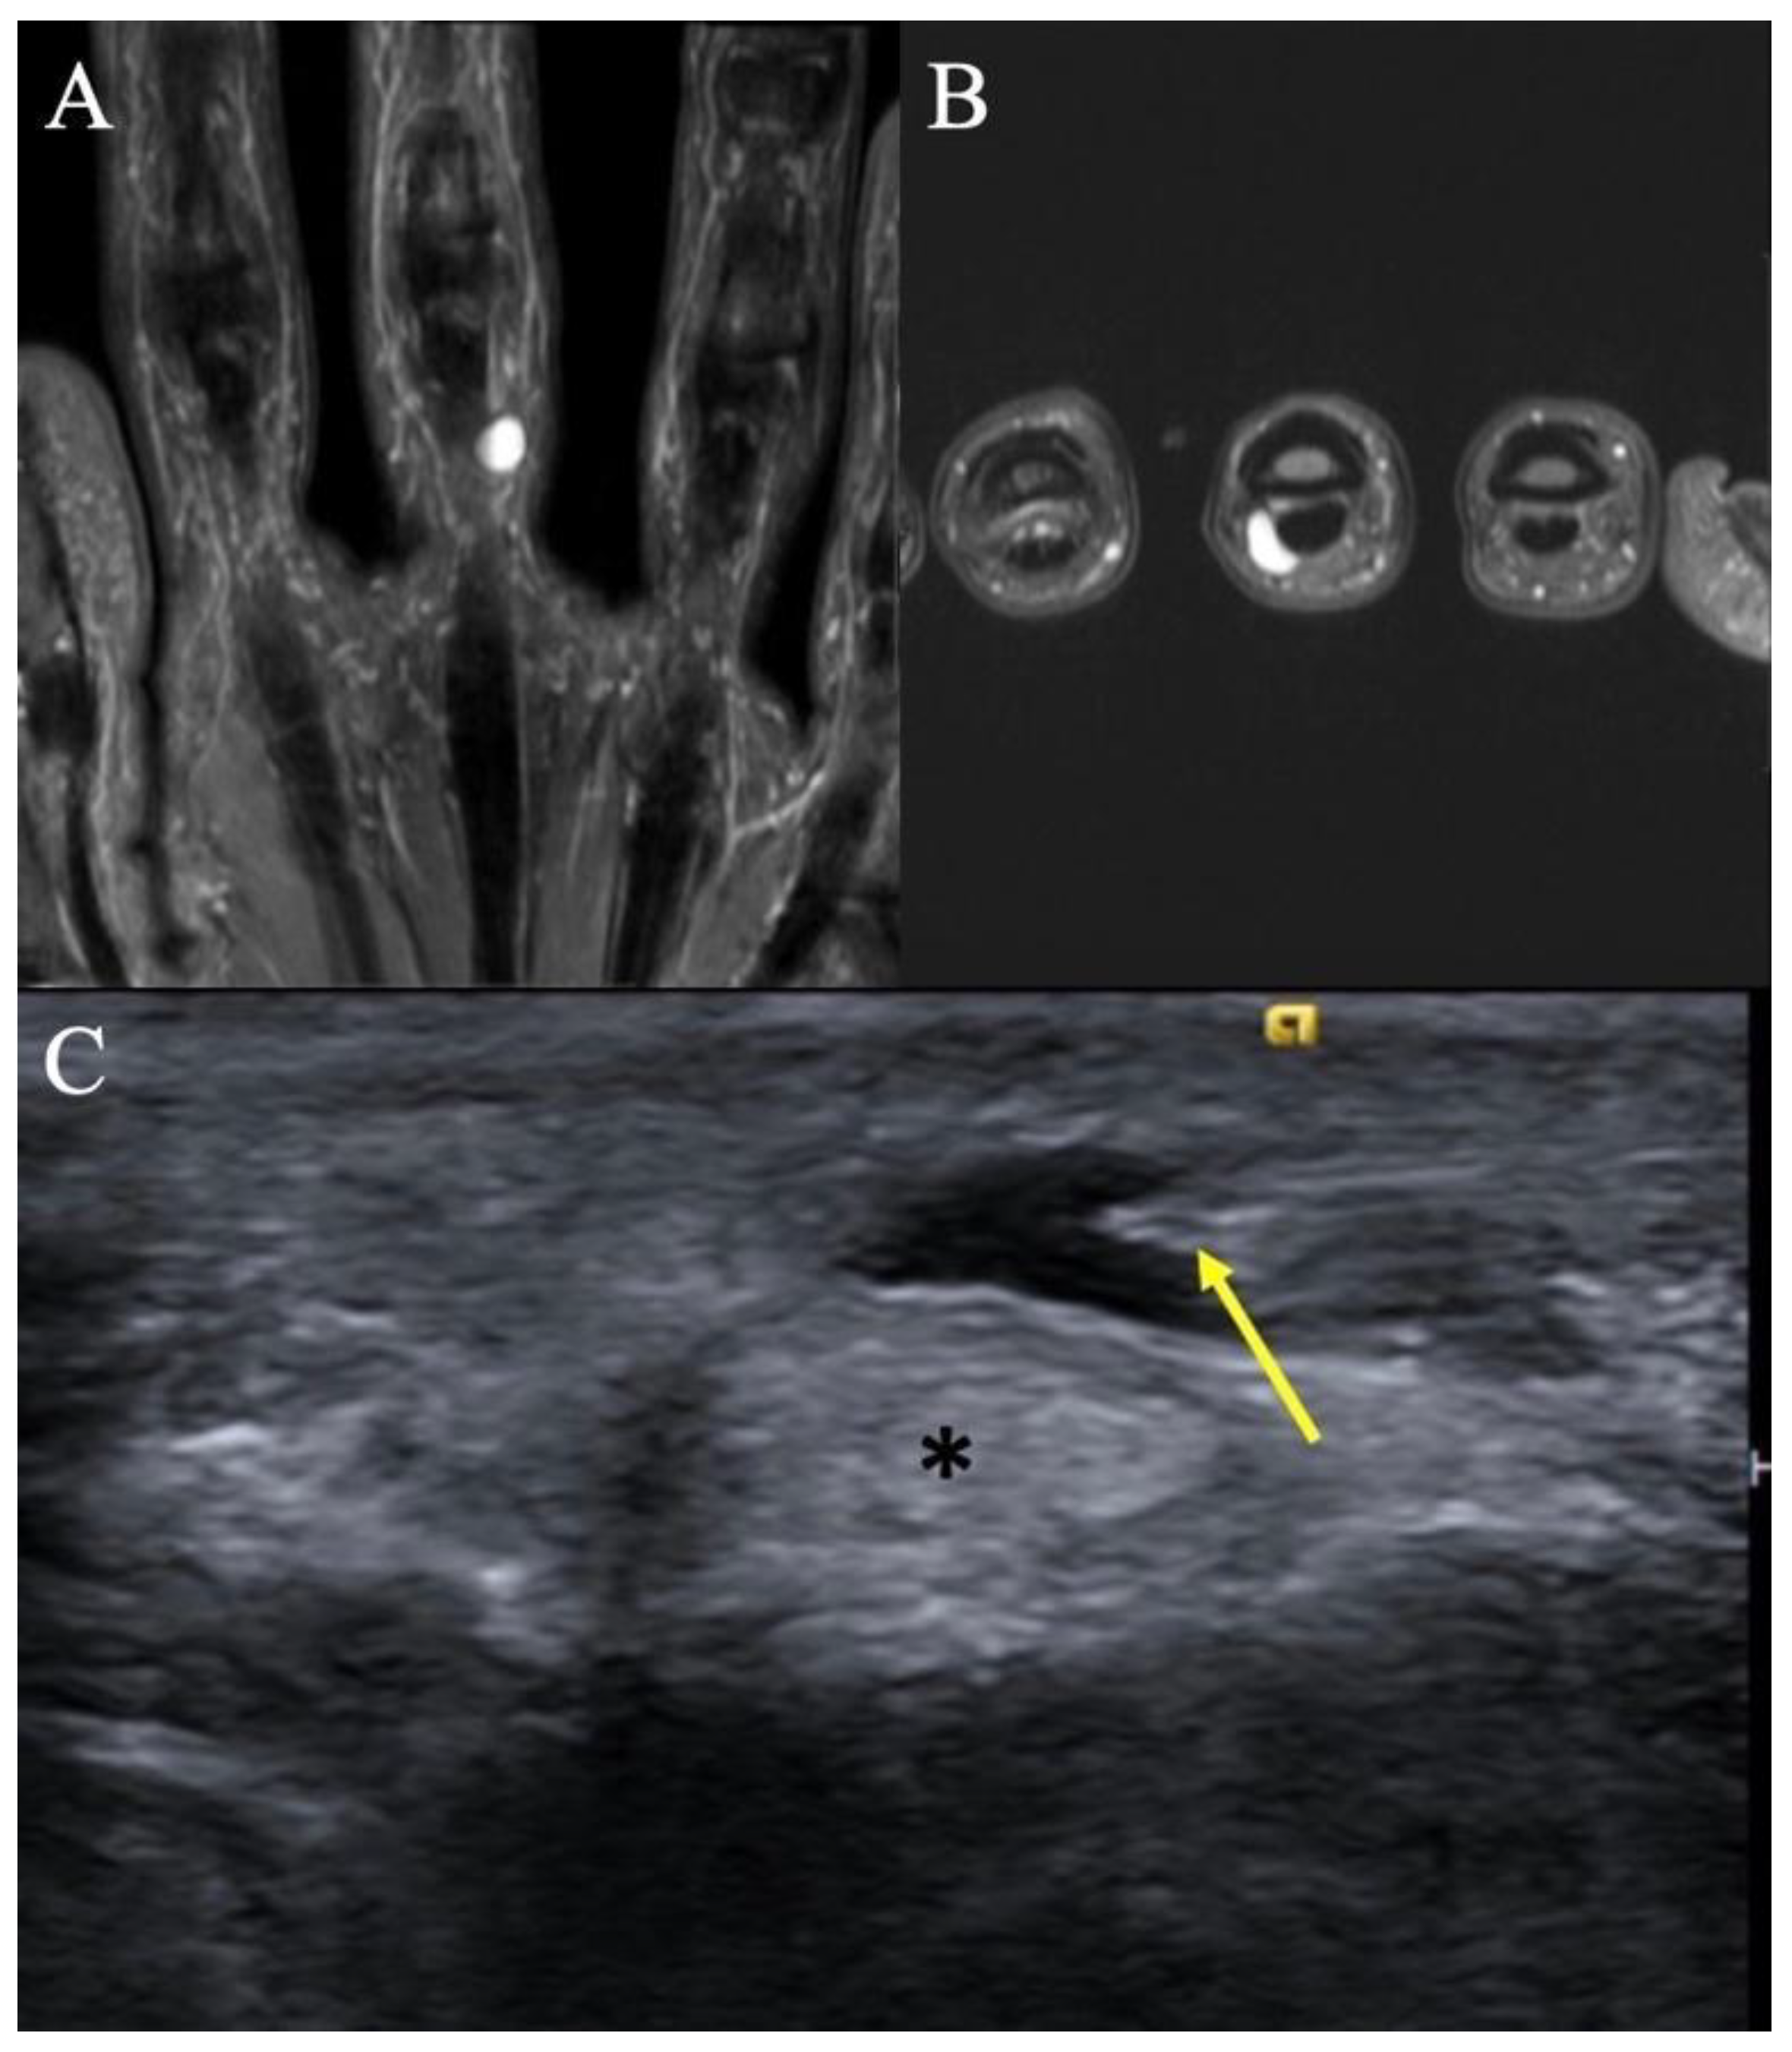

2.5. Glomus Tumors

2.5.1. Clinical Features

2.5.2. Imaging Appearance